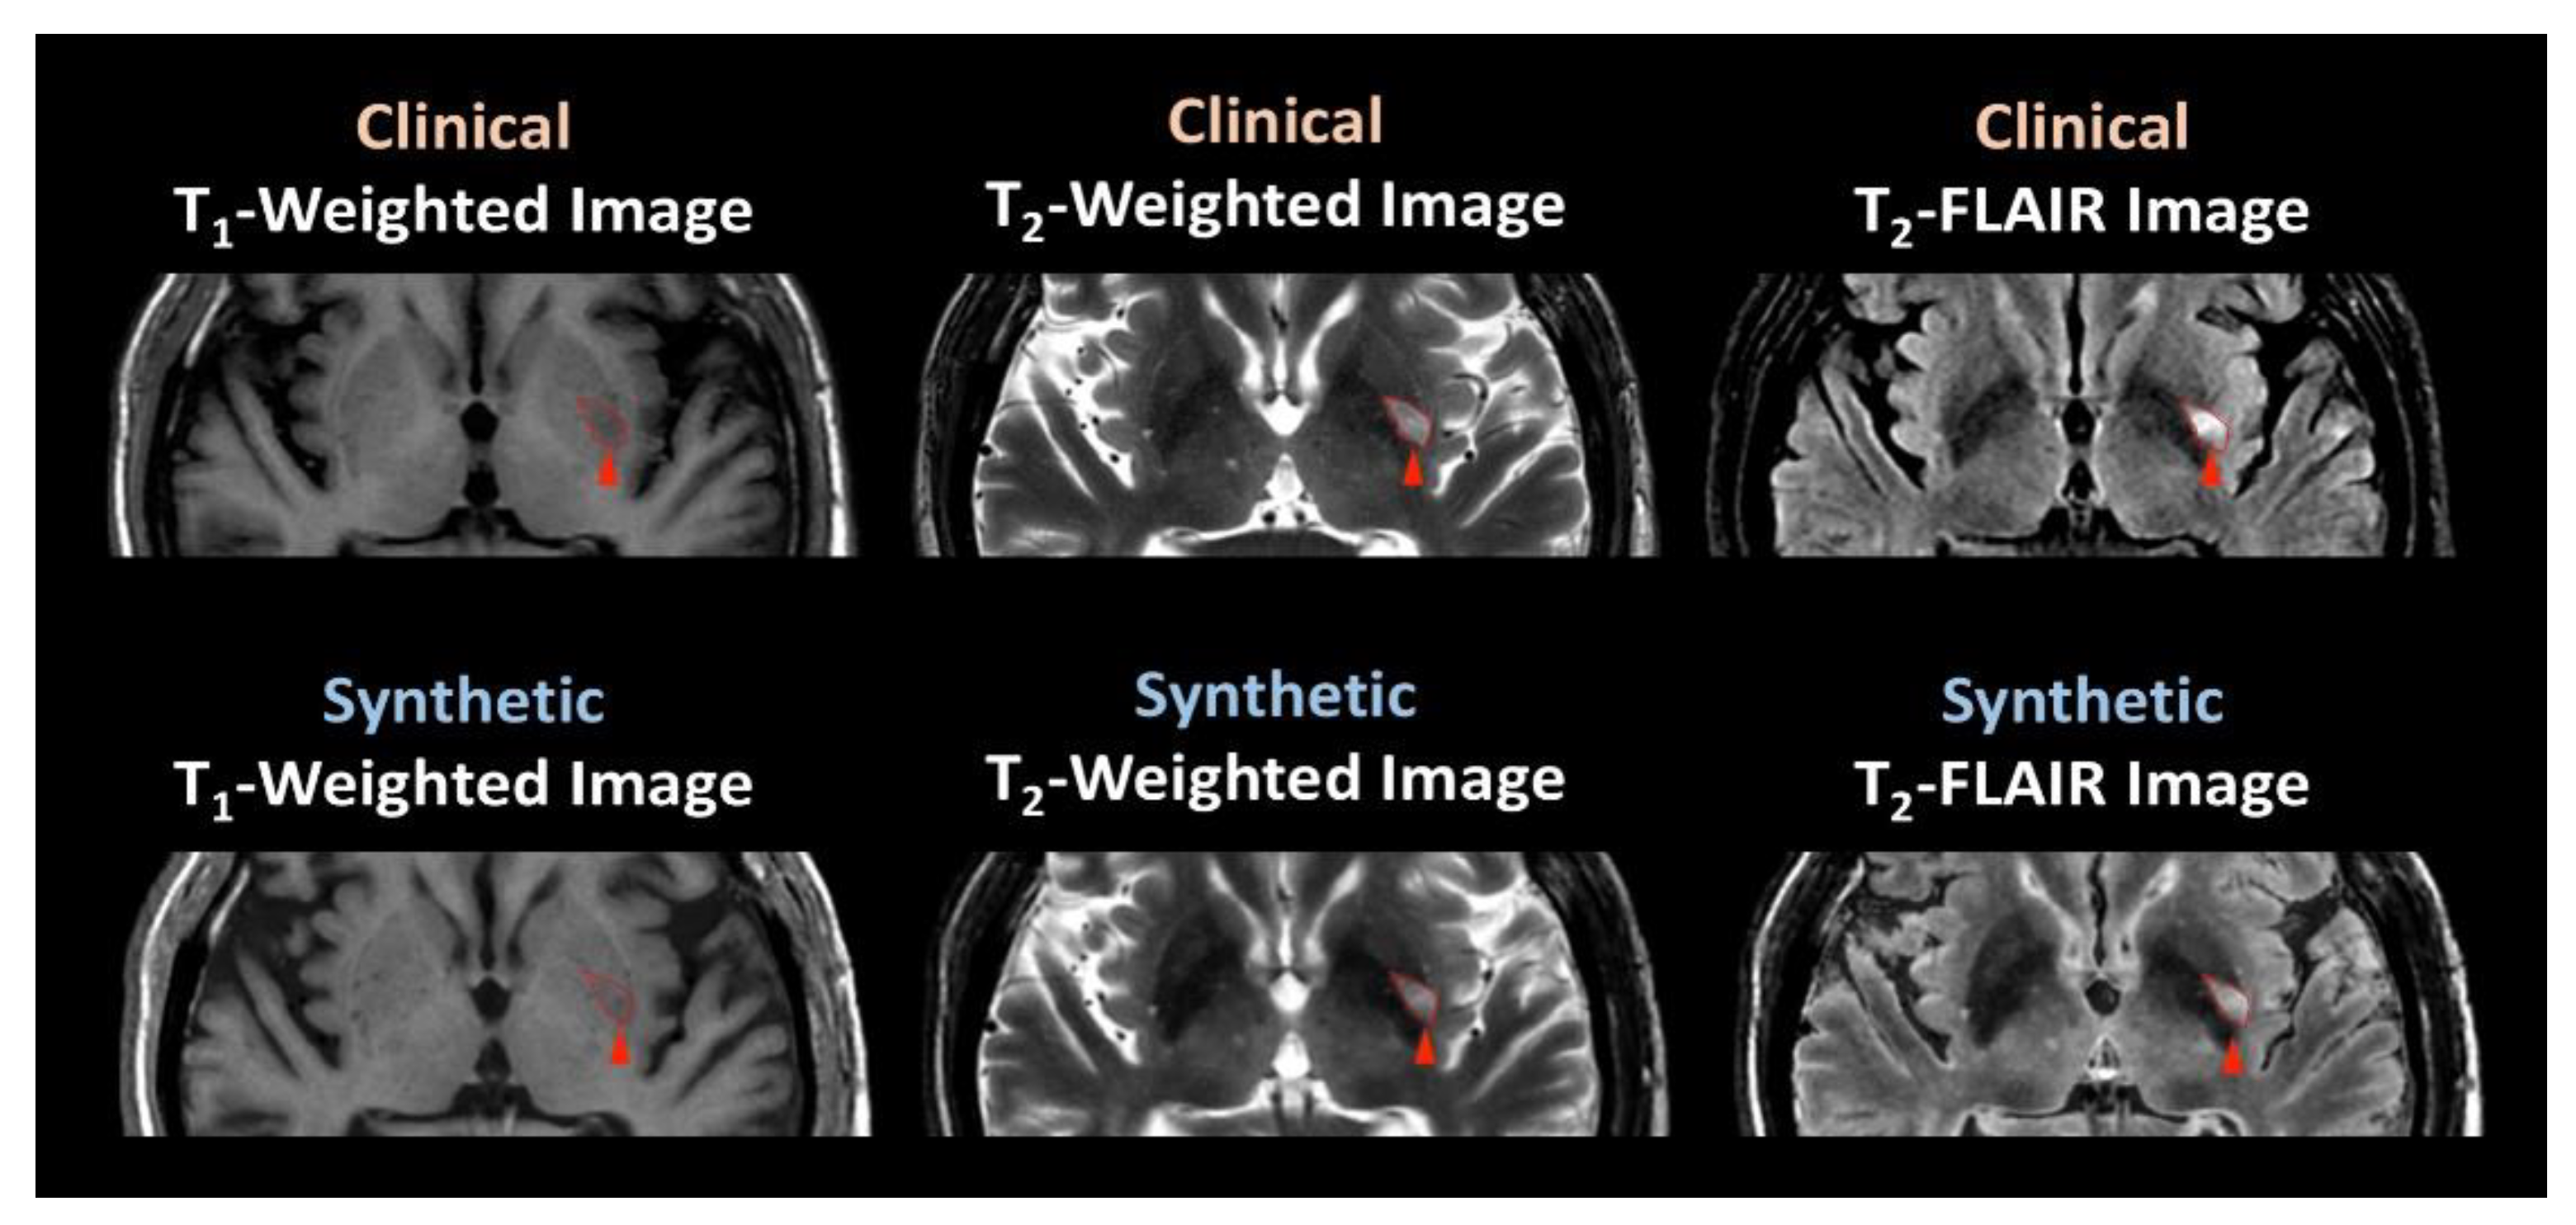

3.2. Participant Evaluation

4. Discussion